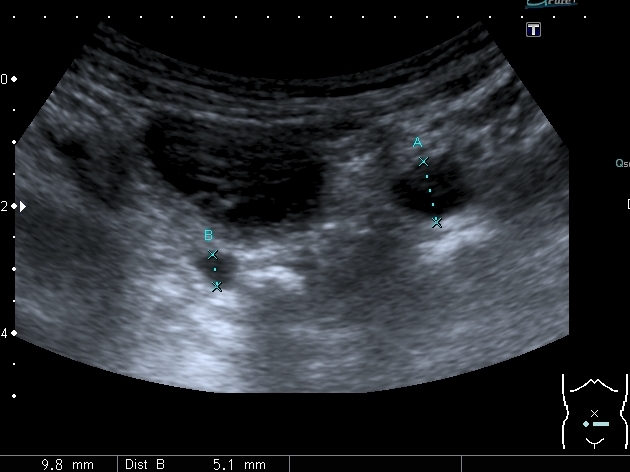

Мочеточники в нижней трети

Нейрогенный мочевой пузырь (?), МКБ, конкремент мочевого пузыря, двухсторонний мегауретер, конкремент правой почки.

Если честно, и я изначально не совсем понял, где находится конкремент (а это конечно же конкремент), локализованный на урограммах. При первичном исследовании на УЗИ его я не видел (либо он спрятался за тенью конкремента мочевого пузыря, либо я обрадовался редкой находке конкремента такого размера в мочевом пузыре - 2.5 см, и не посмотрел что ниже). Тем не менее при ретроспективном анализе архивированных сонограмм, как мне кажется, он попал в один из сканов, м.б. не совсем чётко.

I20111114160229796.jpg

И всё -же, где конкремент :?: